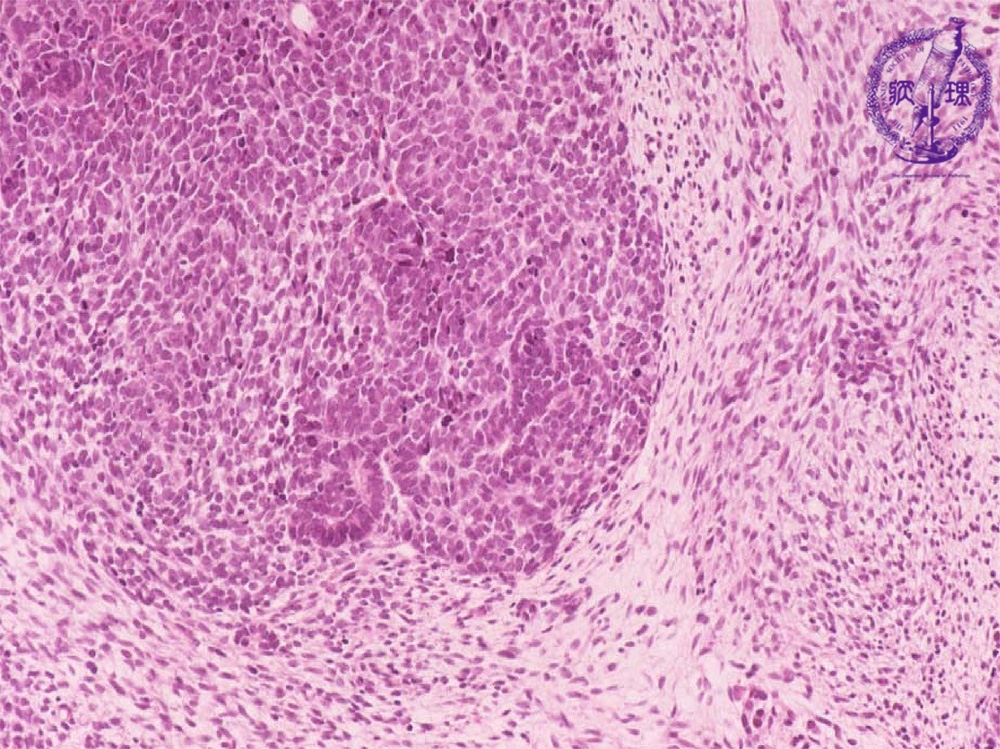

- (16)Nephroblastoma (Wilms tumor)

Microscopic findings ( HE, middle power view): Th tumor is composed of (1) blastemal, (2) organoid and (3) stromal elements (each shown by dotted lines).